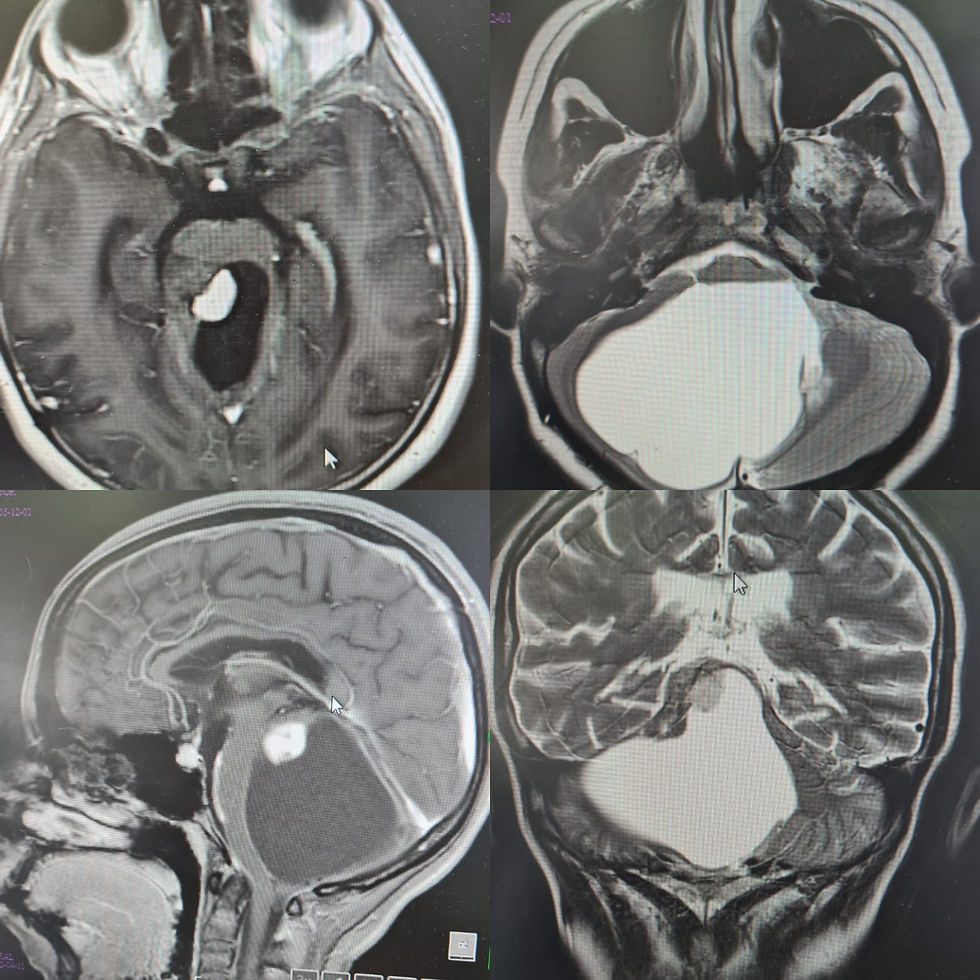

Femenino de 16 años con lesión en fosa posterior, compatible con lesión glial de bajo grado, que ocasionó síndrome cerebeloso. Se realizó drenaje de la porción quística y resección de la porción sólida pegada al tallo cerebral. En el postquirúrgico paciente despierta y sin déficit neurológico agregado.